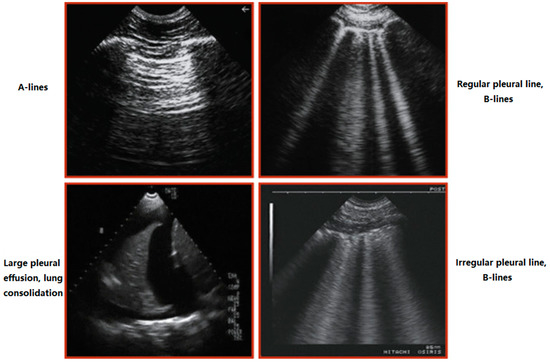

The hallmark of pulmonary congestion (assessed by POCUS) is the presence of bilateral diffuse B-lines (reverberation artifacts of ultrasound waves through edematous interlobular septa, Figure 2) having the following characteristics:

Figure 2.

Main findings in lung sonography. A-lines: Horizontal, echogenic reverberation artifacts beneath the pleural line at multiples of the distance between the ultrasound probe and the visceral-parietal pleural interface, which appear to fatigue as a function of depth. The artifact results from sound reflecting between two parallel reflective surfaces. B lines: They correspond to sub-pleural thickened interlobular septa, absent under normal conditions and present in alveolar-interstitial syndromes. Pleural effusion: Anechoic structure. Lung consolidation: Hypoechoic or isoechoic (hepatization) heterogeneous echotexture. The margin around the consolidation as it abuts normal aerated lung is blurred and irregular. Sonographic air bronchograms appear as multiple hyperechoic millimeter-long air inlets or as hyperechoic branching tubular structures within the consolidated lung parenchyma.